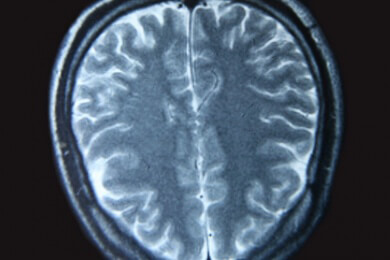

Je nach Art und Schwere des Traumas entstehen in verschiedenen Bereichen des Gehirns sogenannte Läsionen. Dies sind die Verletzungen des Organs an sich.

Aus bisher nicht bekannten Gründen sammeln sich die Plaques unabhängig vom eigentlichen Verletzungsort in den Tiefen des Großhirns an. Oft betroffen ist beispielsweise das Areal "Striatum".